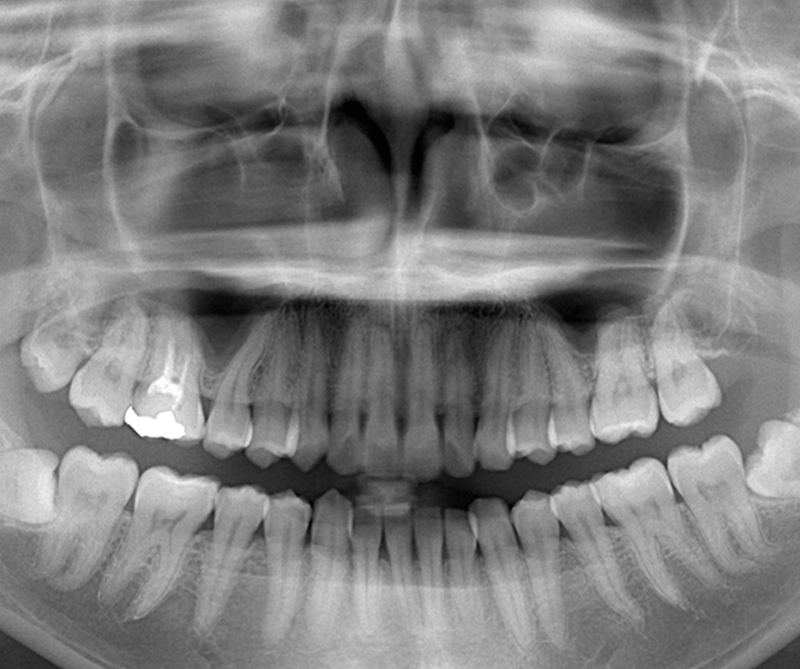

経験豊富な歯科医師、歯科衛生士、歯科助手が「親知らず抜歯専門外来チーム」を作り、技術の研鑽、医療安全の向上に日々全力を尽くしています。

低侵襲な抜歯方法「NEO EXTRACTION」を採用

当院ではピエゾサージェリーという超音波切削器具を用いる低侵襲な抜歯方法を採用しています。

通常のドリルを用いた抜歯と比較して、術後の痛みや腫れが軽減されると言われています。